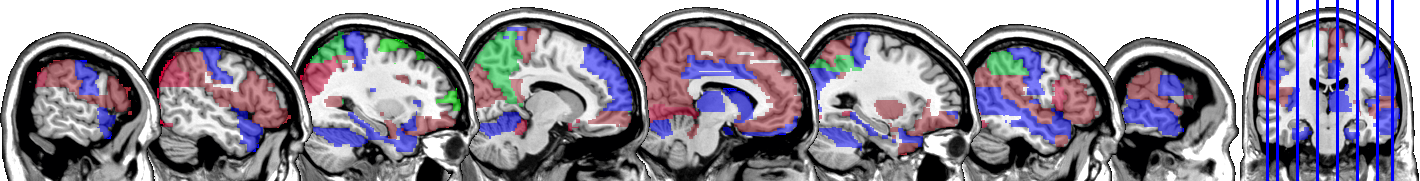

One motivating example for our methods is the application to the functional magnetic resonance imaging (fMRI). The dataset consists of the functional signals of the brain activities measured by blood-oxygen-level-dependent (BOLD), which detects hemodynamic changes based on the metabolic demands followed by neural activities. There are pre-specified regions of the brain, and the BOLD signals associated with multiple voxels in each region are integrated into one signal for that region. Thus, the fMRI data are considered to be multivariate functional data in which each functional predictor represents the signals from a region of the brain. In Section 8, we regress the ADHD index to the regional BOLD activities of the fMRI of the human subjects. There are regions of the brain in the data, and our methods reduce the regions to 41 regions with significantly lower errors than the linear functional regression. Figure 1 displays the regions of the brain’s atlas that are identified by our method. It shows that the methods simplify the data analysis and provide clear representation while keeping the crucial information. The analysis shows that there is an urgent need for new methods in the fields of medical and life sciences as well as other related areas.

In Figure 4 and Figure 5, we display the regions associated with the estimated active sets for IQ and ADHD by the MFG-LASSO respectively. The final active sets of the algorithms were extracted, and matched with the AAL’s atlas where each of the regions has a label. The regions were manually entered into the WFU picked atlas Maldjian and et al. (2003) tool of the SPM-12 ran on MATLAB 2020b to produce mask.nii files. The mask files were imported on MRIcron software to produce the multi-slice images.

The active sets cover the regions associated with IQ in Yoon and et al. (2017) such as cerebello-parietal component and the frontal component. It is mentioned in the paper that the parietal and the frontal regions are strongly associated with intelligence by maintaining a connection with the cerebellum and the temporal regions. The shaded areas cover the ones mentioned in Goriounova and Mansvelder (2019) as well. We provide the name of the regions associated with these active sets in the appendix.

It is interesting that ADHD and IQ have a large proportion of common active sets. For instance, when MFG-LASSO is applied, they overlap in ROIs where the size of active sets are and for IQ and ADHD respectively. On the other hand, the ROIs that are associated with ADHD but not with IQ are the middle and superior frontal, the Parahippocampal, the inferior parietal, and the superior temporal pole gyri. The ratio of the number of right hemisphere regions to the left ones associated with IQ is significantly greater than that of ADHD.